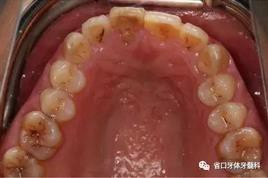

1.?病例簡介 43歲女性患者,主拆:右上前牙松動(dòng)不適數(shù)日要求修復(fù)?,F(xiàn)病史:患者數(shù)年前右上前牙因“齲壞”于外院行根管治療(具體不詳),數(shù)日前牙冠松動(dòng)不適,現(xiàn)覺影響咀嚼及美觀,遂來我院要求進(jìn)一步診治。否認(rèn)高血壓、心臟病等重大疾病,否認(rèn)結(jié)核、肝炎等傳染病史,否認(rèn)手 術(shù)、輸血史等,未發(fā)現(xiàn)藥物過敏。無吸煙習(xí)慣。臨床檢查:口外觀顏面基 本對稱,皮膚無紅腫破潰,顳下頜關(guān)節(jié)區(qū)無彈響、雜音、壓痛,開口度約 37mm,開口型“↓”,頜下、刻下和頸部未及腫大淋巴結(jié)。中位笑線??趦?nèi)檢查,口腔衛(wèi)生可,色素(+),BOP(-),PD=2mm,上頜右側(cè)中切 牙冠部變色,冠根折斷至齦下3mm,叩不適,松動(dòng)Ⅱ°~Ⅲ°。牙齦稍紅, 齦緣水平及齦乳頭高度可,屬于中厚齦生物型,附著齦寬度約5mm,唇系帶附著可。上頜右側(cè)中切牙缺牙間隙與對側(cè)同名牙一致,約>7mm,修復(fù)空 間良好。與對頜牙覆合覆蓋正常。MCT檢查示上頜右側(cè)中切牙冠根折斷至骨 下,根管內(nèi)見充填物,根充不全,根尖見陰影,大小約3mm×3mm。牙槽窩根方可用骨量可,唇側(cè)骨壁完整,冠方骨壁厚度約1mm。

圖1 術(shù)前口內(nèi)照

圖2 術(shù)前口內(nèi)照

圖3 術(shù)前口內(nèi)照